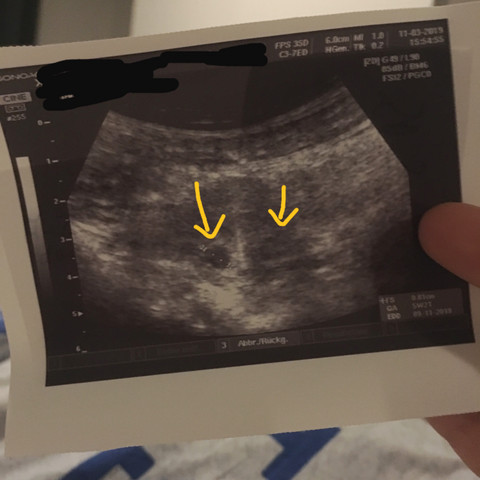

2 Fruchthohle Auf Ultraschall Ubersehen Schwangerschaft Gynakologie Zwillinge